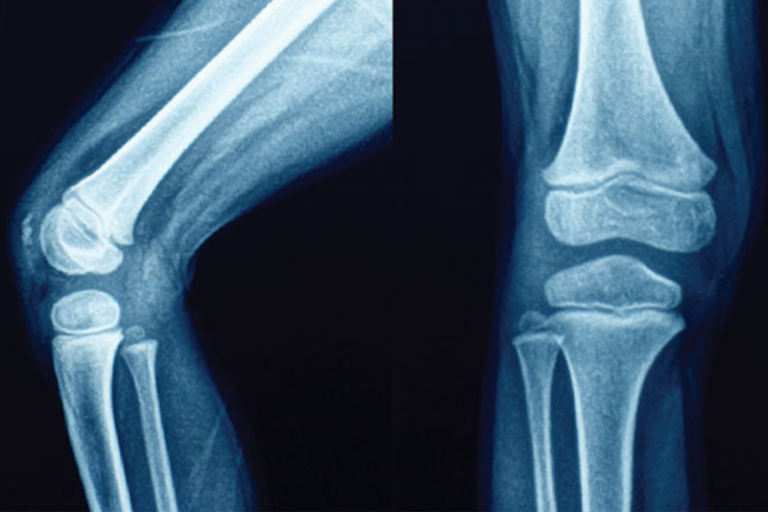

幾乎每個人都曾有扭扭脖子,扳扳手指頭或彎膝關節產生「咔咔」響的經驗,為何會有這聲音的產生?這樣的聲音是好還是不好呢?脊椎矯正(Chiropractic treatment)時會有這樣的聲音是正常的嗎?

最近一些研究有了答案。主要是當關節初「動」時,肌腱的作用力(如拉力等)會瞬間先使關節產生形變,最多可增大至7%,形變產生關節腔負壓。這負壓雖微,但足以使關節囊凹陷(被吸入),使溶於滑液內的氮氣、氧氣、二氧化碳等氣體,部分氣化成氣泡。累積在人體的關節之間,降低關節的潤滑度,使關節變得較僵硬,當我們折指頭、做體操或其他大動作時,關節內的相對活動加大,把氣泡擠破便會發出聲音(當然,有時伴隨著關節內骨骼相互磨擦的聲響),關節也會有較舒服、開展的感覺;但是氣泡被擠破,其實仍然存在關節內,因此過一段時間,又會聚積在一起,又可以發出聲音。